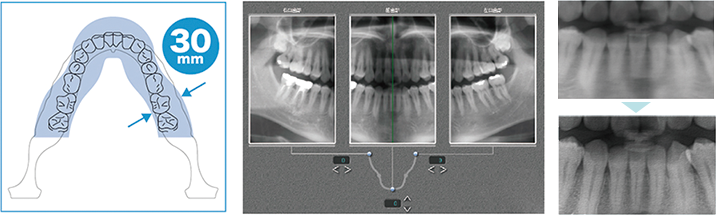

Tomosynthesis

SolioXZ 的 2D 攝影並非完全平面, 它帶有 30 mm的厚度, 而每 1 mm的間隔有 31 張切片。

*注意兒童和正面攝影會有些許不同。拍攝完成後系統會自動顯示前牙最清晰的影像,這個功能可以有效的排除因定位不佳而產生的前牙區模糊影像。 當然, 使用者也可自行挑選前後左右部位最滿意的切片組合成一張完整的全口影像。

*注意儲存之後無法修改。